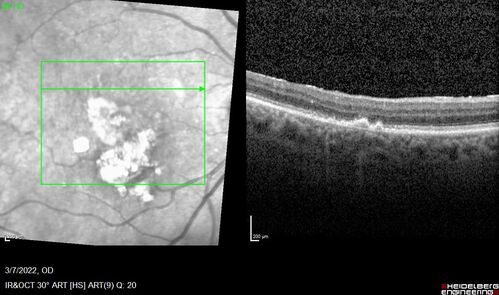

Pigment epithelial detachment with cholesterol crystals

Onion sign

Pigment epithelial detachment with cholesterol crystals - onion sign